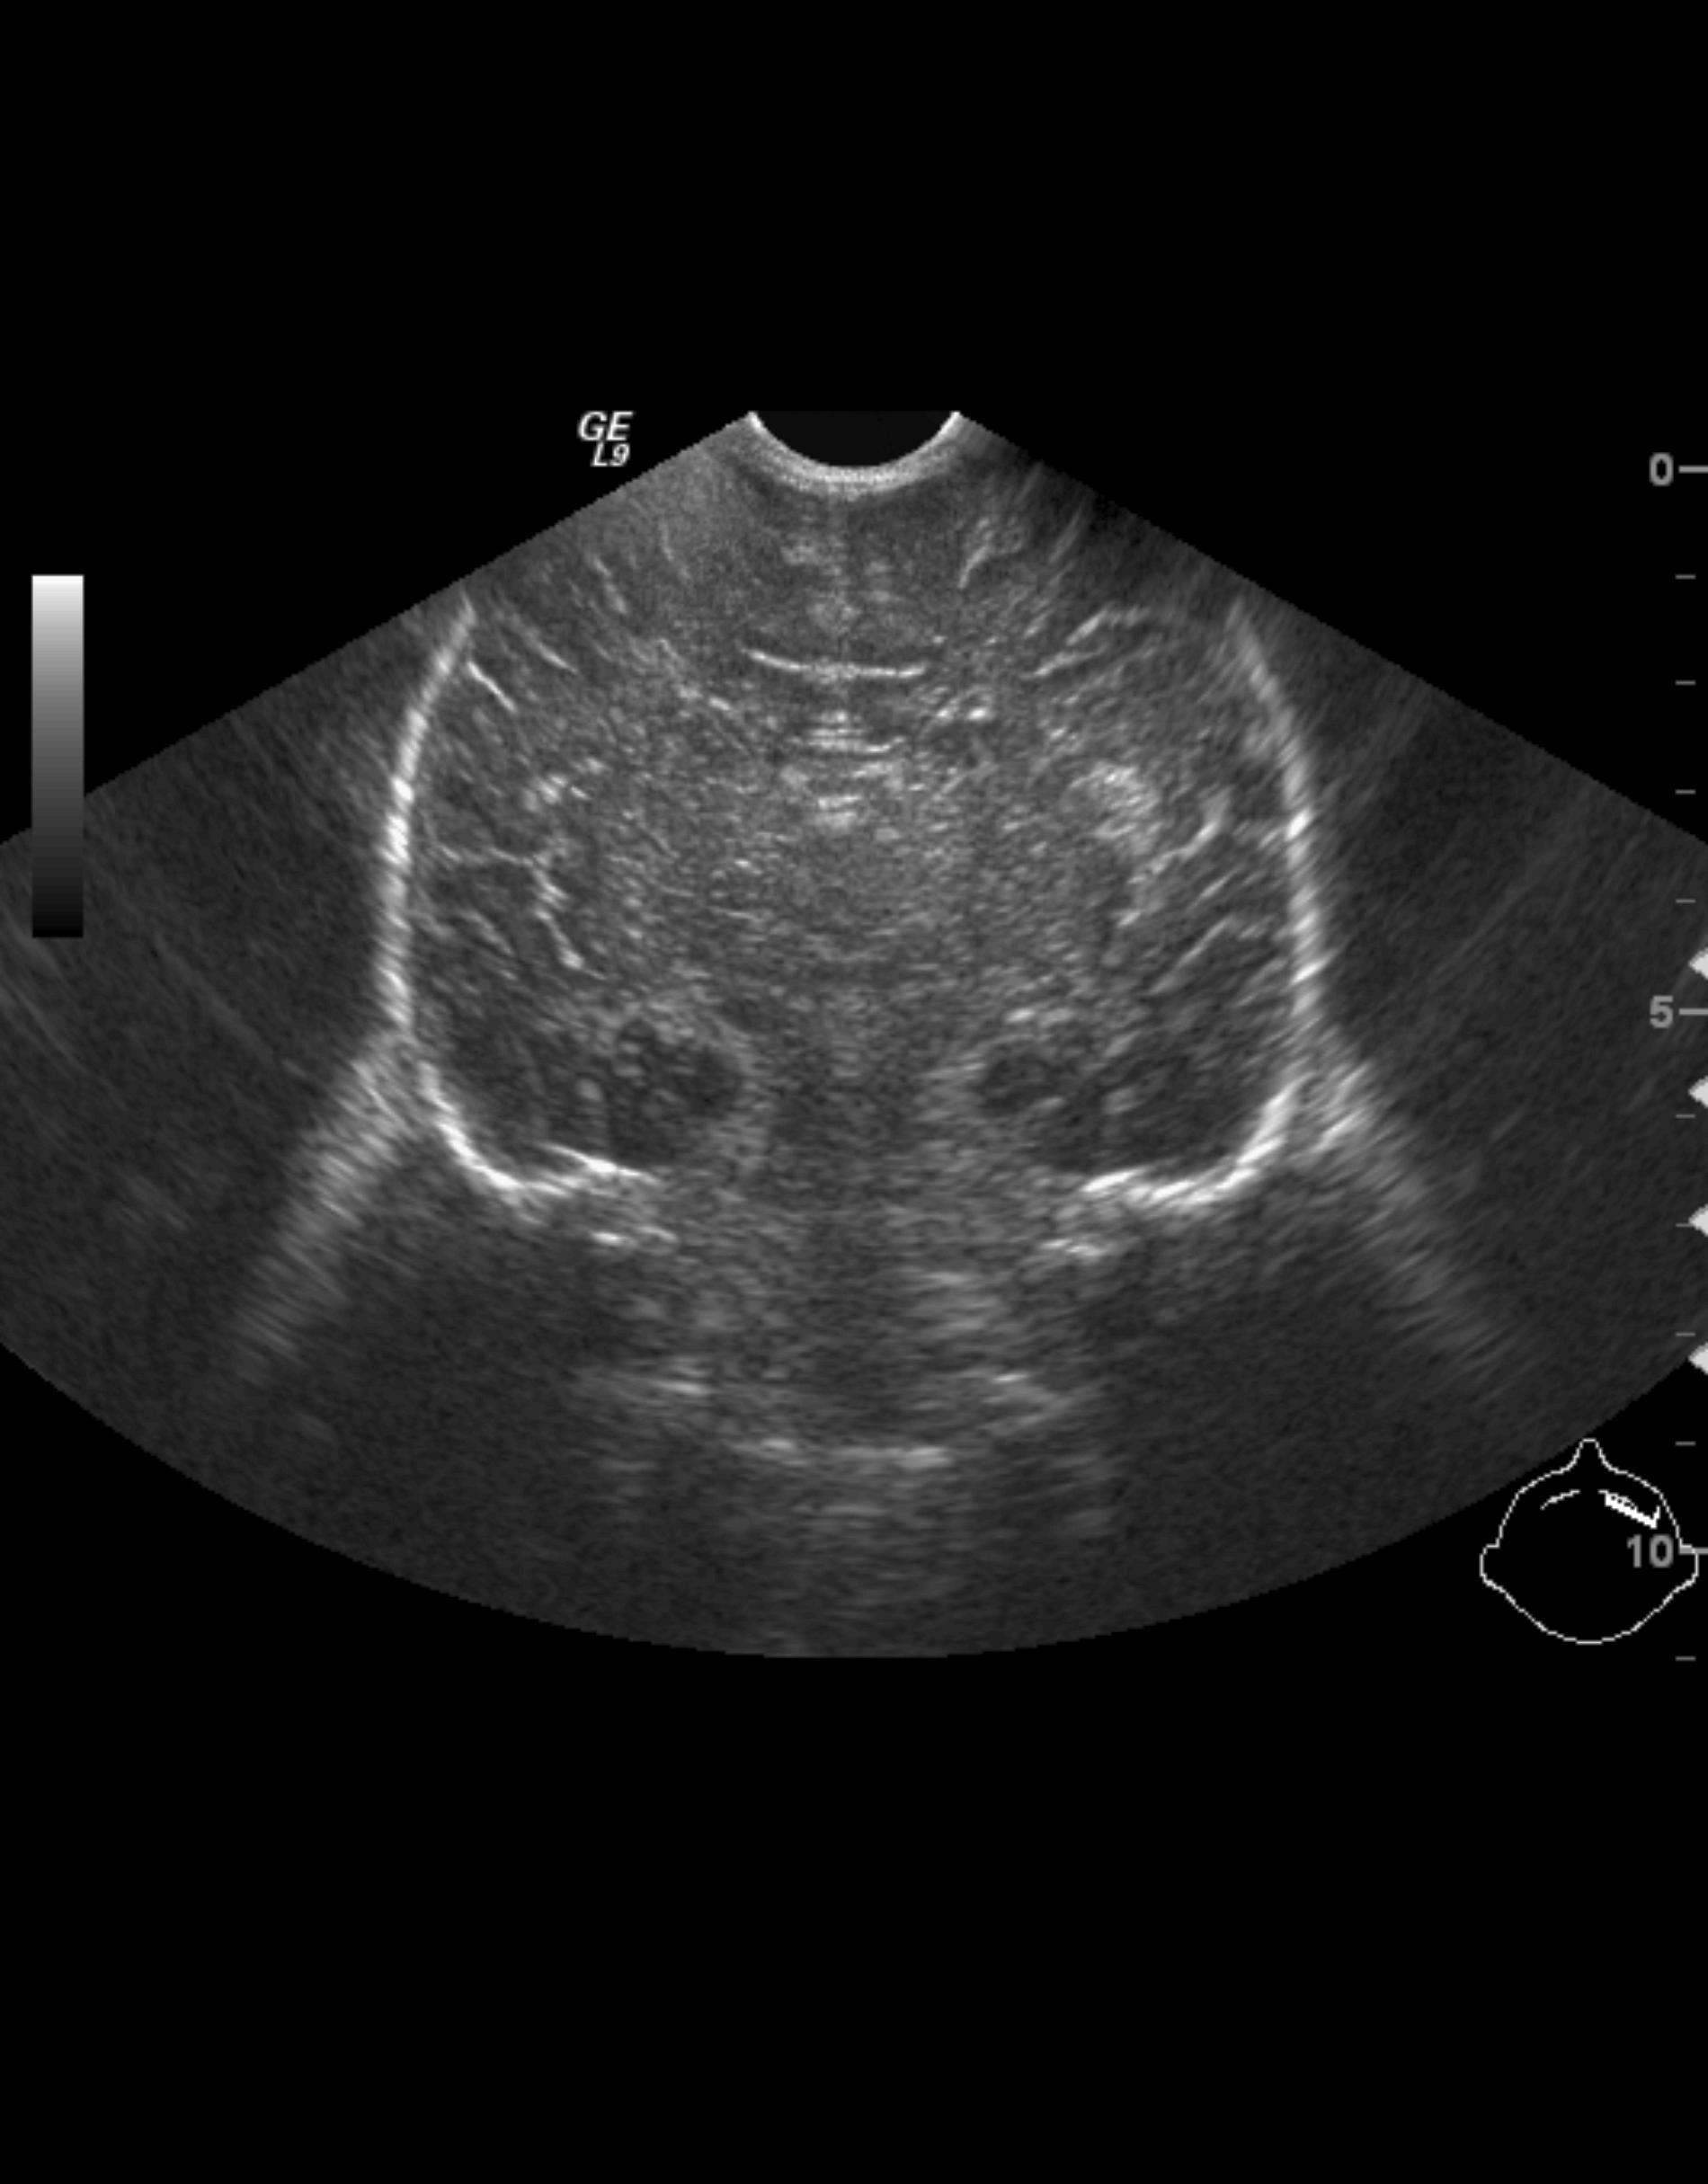

Uretropelvic obstruction (UPO). Uretropelvic junction stenosis can be an acquired or an innate state, with different degrees that lead to the dysfunction of excretion of urine from the pyelon to the proximal ureter. It is the most frequent form of obstructive uropathy. US examination even at prenatal states can diagnose the urinary tract dilatation that can be uni- or bilateral, always without ureter dilatation.

Image

22.The calices and the pyelon of the kidney are markedly dilated, the parenchyma is thinner. Severe hydronephrosis. The ureter is not visible. Pyelouretral stenosis.